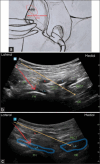

Femoral rami obturator nerve trunk (FRONT) block in intramedullary nailing surgery: A motor-sparing approach to anterior hip analgesia